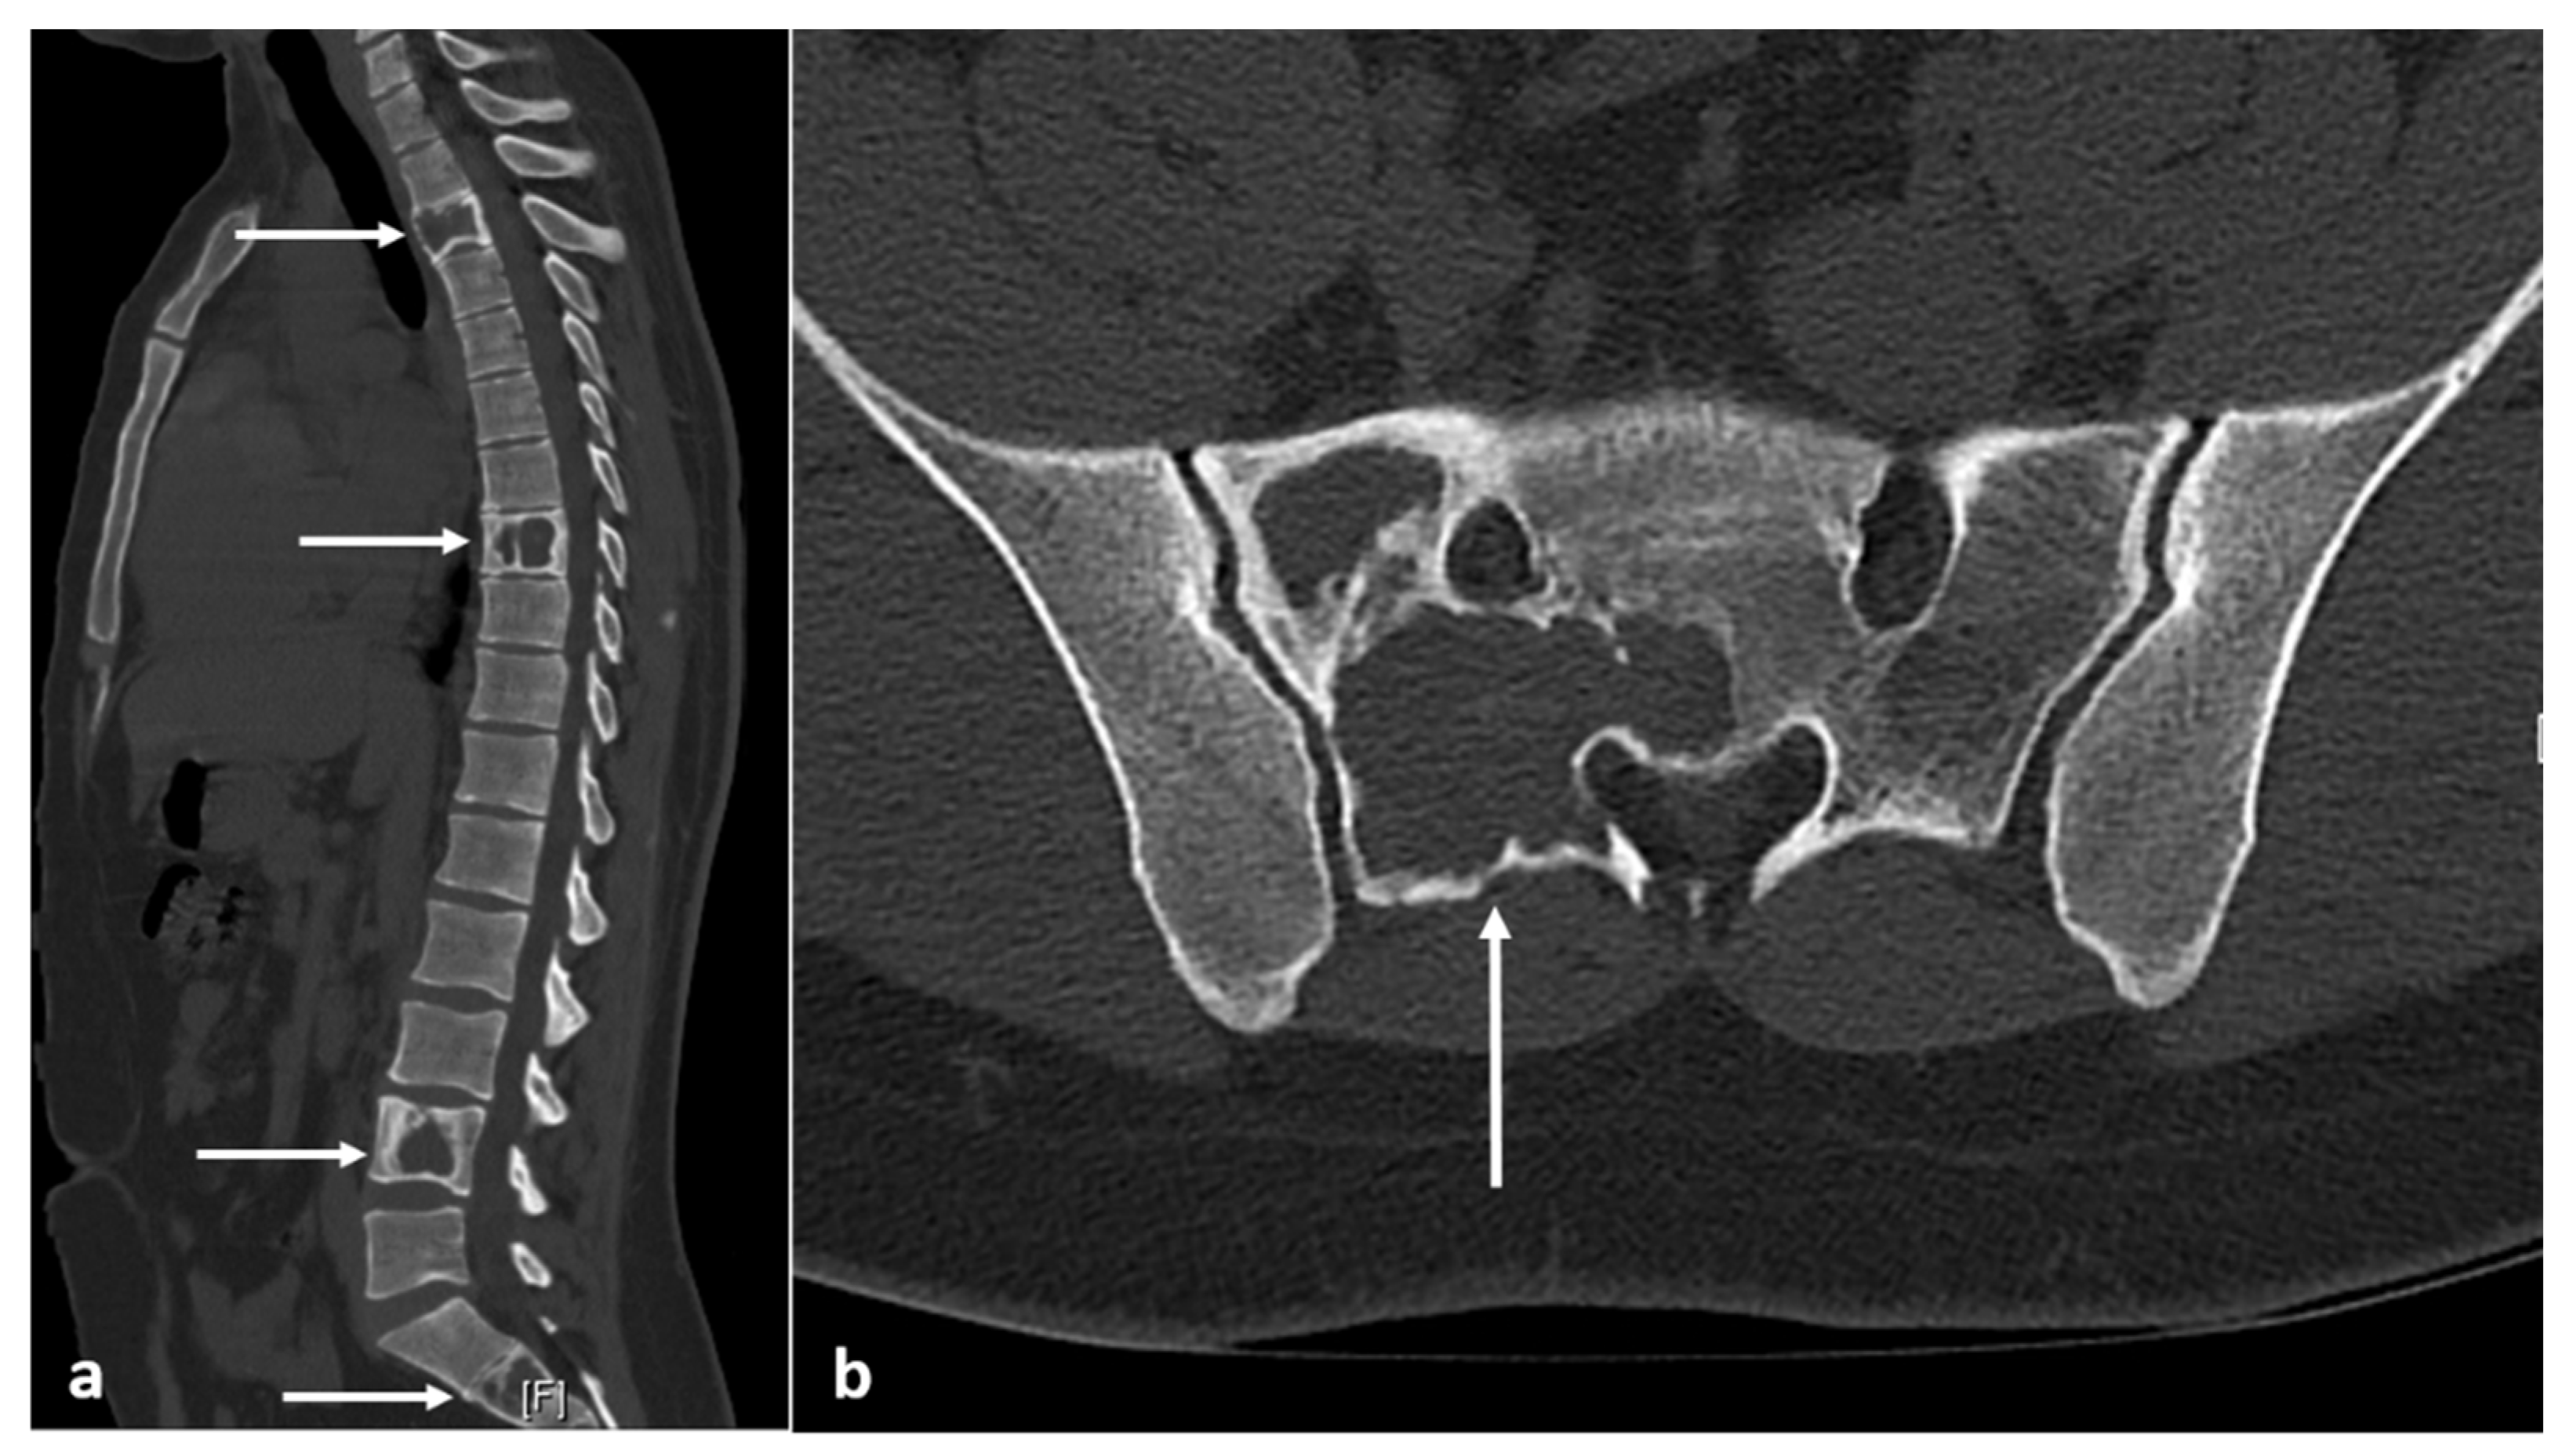

3.4. Fibrous Dysplasia

| Fibrous dysplasia | Ground glass matrix. Cystic areas can appear lytic. | Low on T1 and intermediate to high on T2. Cystic areas are hyperintense on T2 and STIR. |